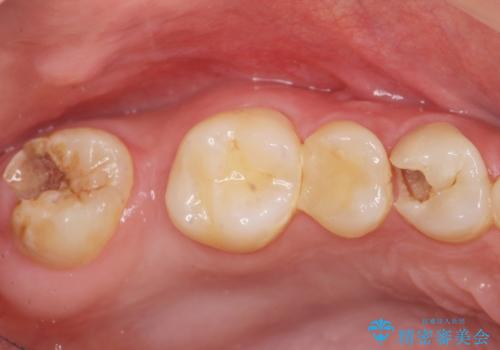

- 上下1本づつの歯を失い、噛めないことの改善を求めて来院されました。

保存可能な歯の虫歯・根管治療を行い、喪失した部分はインプラントを埋入、オールセラミックジルコニアクラウンを製作し審美的に仕上げていきます。